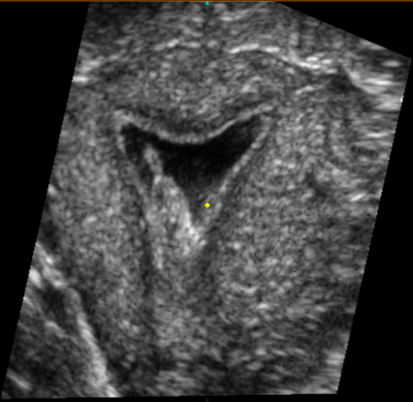

Современные экспертные УЗИ сканеры дают возможность проводить исследования всех органов в 3D. Это позволяет, используя полученный массив данных, получать диагностические сечения в любой плоскости, недоступной для обычного 2D УЗИ. Наиболее интересной является фронтальная. Например, визуализация полости матки. Диагностическая возможность выявления пороков развития превосходит все другие методы (рентгеновские и МРТ). Метод также позволяет уточнить положение ВМК (спирали) в полости матки, расположение миоматозных узлов, расположение плодного яйца на малых сроках, полипов. Сегодня современное экспертное ультразвуковое исследование невозможно без использования 3D УЗИ.